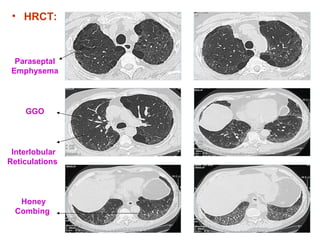

A 63-year-old male with a history of prostate adenocarcinoma and COPD presented with worsening dyspnea on exertion and significant weight loss. Examination revealed paraseptal emphysema and combined pulmonary fibrosis with emphysema syndrome (CPFE), with evidence of pulmonary hypertension. Despite partial improvement with steroids, the patient experienced progressive symptoms, necessitating further investigations.